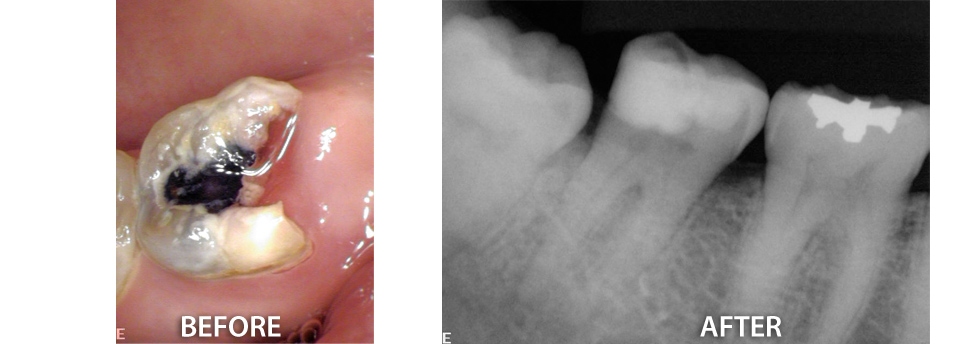

Our office offers a variety of surgical procedures designed to improve oral health and eliminate pain. We help with extractions of impacted wisdom teeth and retained “baby” teeth that are in the way of erupting permanent teeth. Other treatments include removal of excess or swollen gums around erupted or partially erupted teeth and elimination of problem tissue causing periodontal problems. In those cases where the complexity dictates, we have teamed up with surgery specialists that help us make procedures smooth and easy. Click here to find out more.